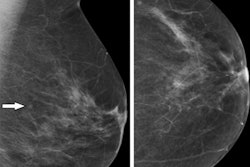

(Left) Area with fracture (in the box). This may not be easily picked up by an inexperienced radiographer. (Right) An AI-generated heatmap, directing the radiographer to check the area. Figure courtesy of Clare Rainey and MURA dataset.The survey highlights issues with the perceptions of reporting radiographers in the U.K. regarding the use of AI for image interpretation, according to Rainey.